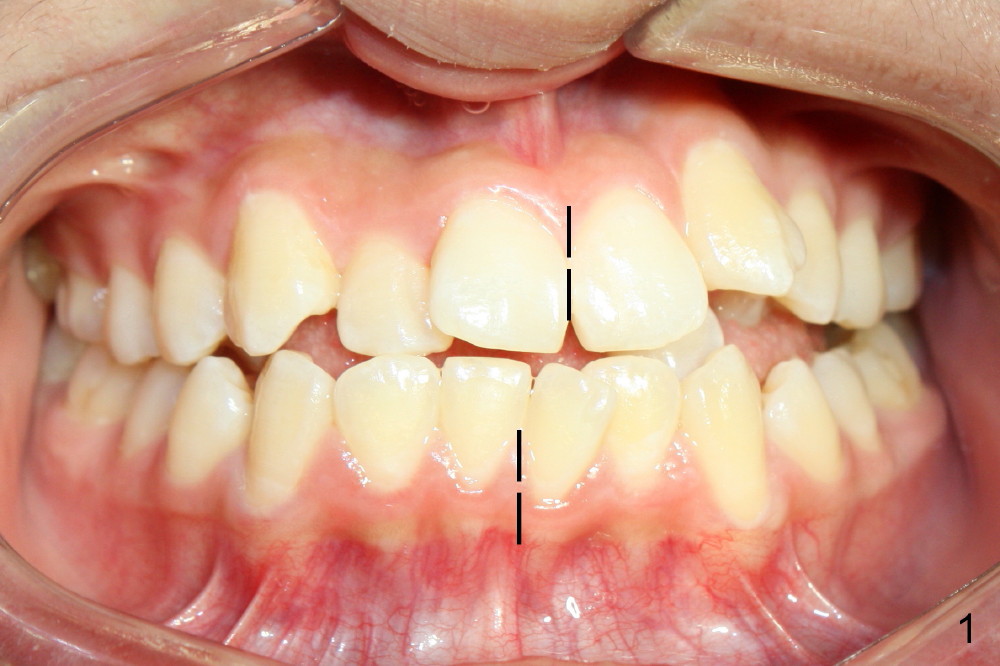

David, 16 years old, has severe crowding, midline deviation (Fig.1: dashed lines), and UL2 complete blockout (Fig.3: 2). Orthodontic treatment starts with extraction of four of the 1st bicuspids (Fig.2,3: .014 Niti).